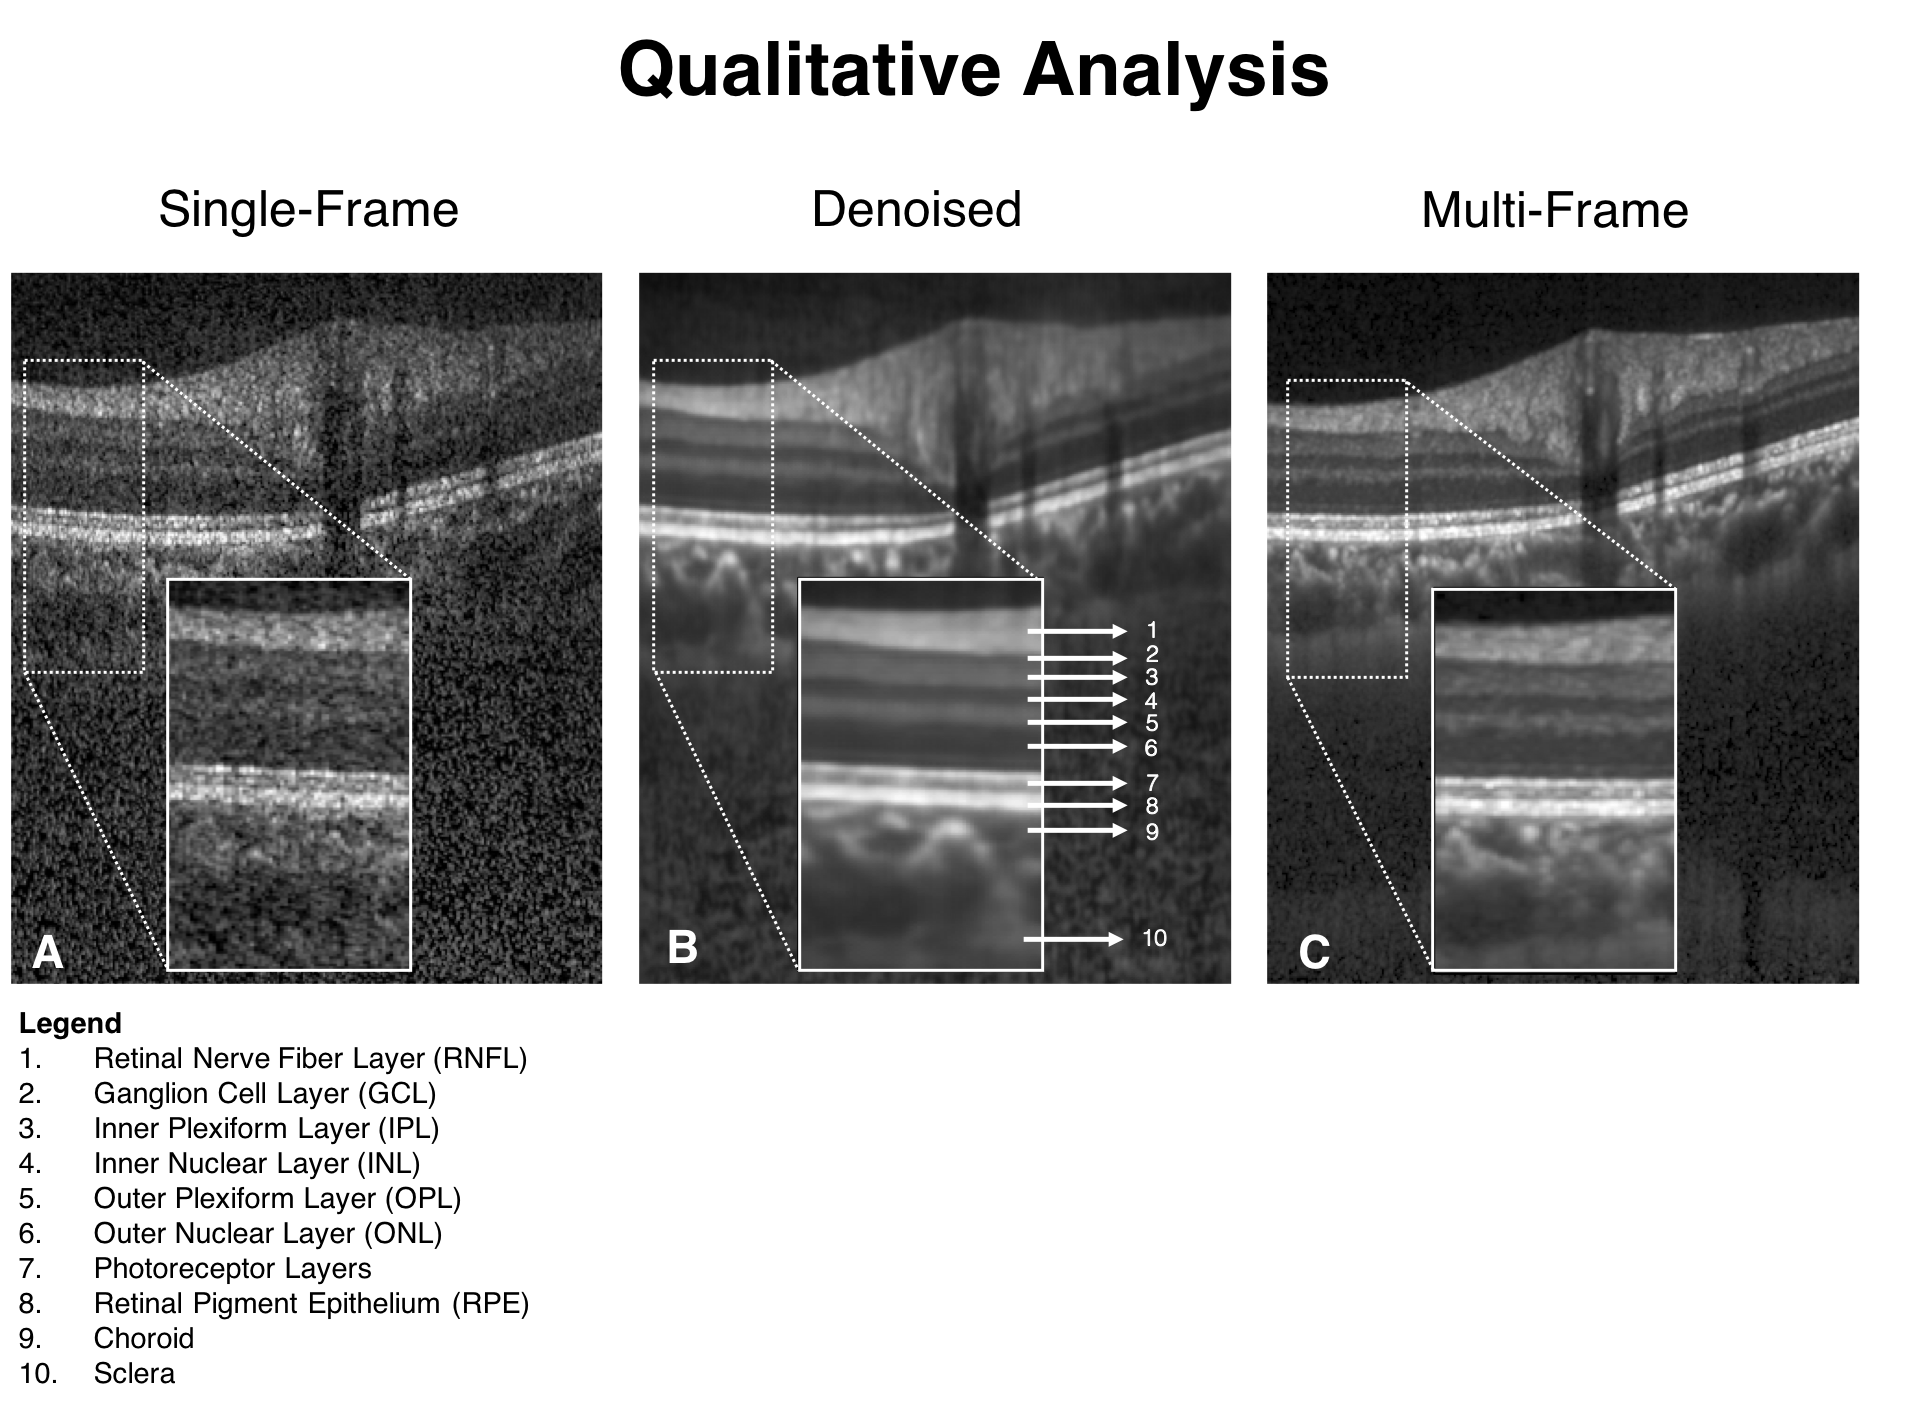

When trained with the ‘clean’ B-scans (multi-frame) and the corresponding ‘noisy’ B-scans, our network was able to successfully denoise unseen single-frame B-scans. The single-frame, denoised and multi-frame B-scan for a healthy subject can be found in (Figure 3). In all the cases, the denoised B-scans were qualitatively similar to their corresponding multi-frame B-scans (Figure 4). Overall, the visibility of all ONH tissues were prominently enhanced (Figure 3; B).

Refer to caption

Figure 3: Single-frame (A), denoised (B), and multi-frame (C) B-scans for a healthy subject are shown. The denoised B-scan can be observed to be qualitatively similar to its corresponding multi-frame B-scan. Specifically, the visibility of the retinal layers, and choroid, and lamina cribrosa were prominently improved. Sharp and clear boundaries were also obtained for retinal layers, and the choroid-scleral interface.

Using the proposed network, we obtained denoised B-scans that were qualitatively similar to their corresponding multi-frame B-scans (Figure 3) and (Figure 4), owing to the reduction in noise levels. The mean SNR for the denoised B-scans was 8.14±1.03plus-or-minus8.141.038.14\pm 1.03 dB, a two-fold improvement (reduction in noise level) from improvement from 4.02±0.68plus-or-minus4.020.684.02\pm 0.68 dB that was obtained for the single-frame B-scans, thus offering an enhanced visibility of the ONH tissues. Given the significance of the neural (retinal layers) [79, 80, 81, 82, 83] and connective tissues (sclera and LC) [84, 85, 86, 87, 88], in ocular pathologies such as glaucoma [2], and age-related macular degeneration [89], their enhanced visibility is critical in a clinical setting. Furthermore, reduced noise levels would likely increase the robustness of aligning/registration algorithms used to monitor structural changes over time [18]. This is crucial for the management of multiple ocular pathologies [90, 91].

In denoised B-scans (vs single-frame B-scans), we consistently observed higher contrast across tissues. Our approach enhanced the visibility of small (e.g. RPE and photoreceptors) and low-intensity tissues (e.g. GCL and IPL; Figure 3 B). For all tissues, the mean CNR increased from 3.50±0.56plus-or-minus3.500.563.50\pm 0.56 (single-frame) to 7.63±1.81plus-or-minus7.631.817.63\pm 1.81 (denoised). Since existing automated segmentation algorithms rely on high contrast, we believe that our approach could potentially reduce the likelihood of segmentation errors that are relatively common in commercial algorithms [15, 16, 17, 92]. For instance, the incorrect segmentation of the RNFL can lead to inaccurate thickness measurements, leading to under-/over- estimation of glaucoma [19]. By using the denoising framework as a precursor to automated segmentation/thickness measurement, we could increase the reliability [93] of such clinical tools.